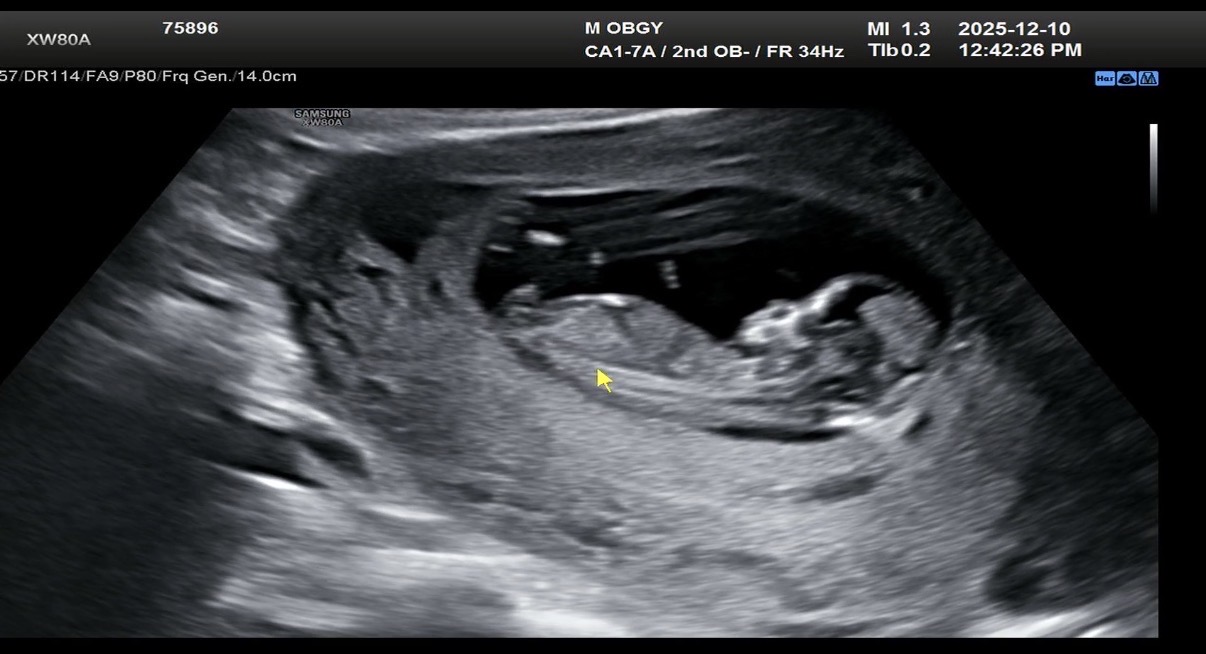

12주차 성별 봐주세요!

아들일까요 딸일까요!